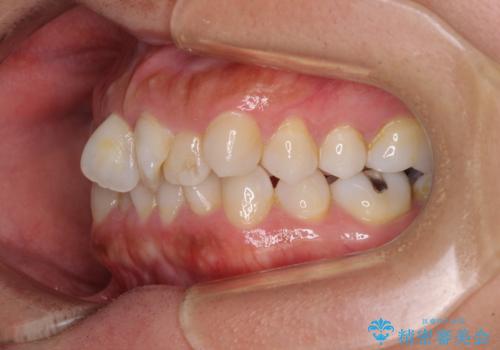

右上と左下の小臼歯が1本ずつ欠損しており、奥歯の咬み合わせが乱れている状態でした。

骨格的な左右差があり、上下正中をぴったり合わせることは難しく、奥歯の咬み合わせの調整にも時間がかかりましたが、きれいに整えることができました。